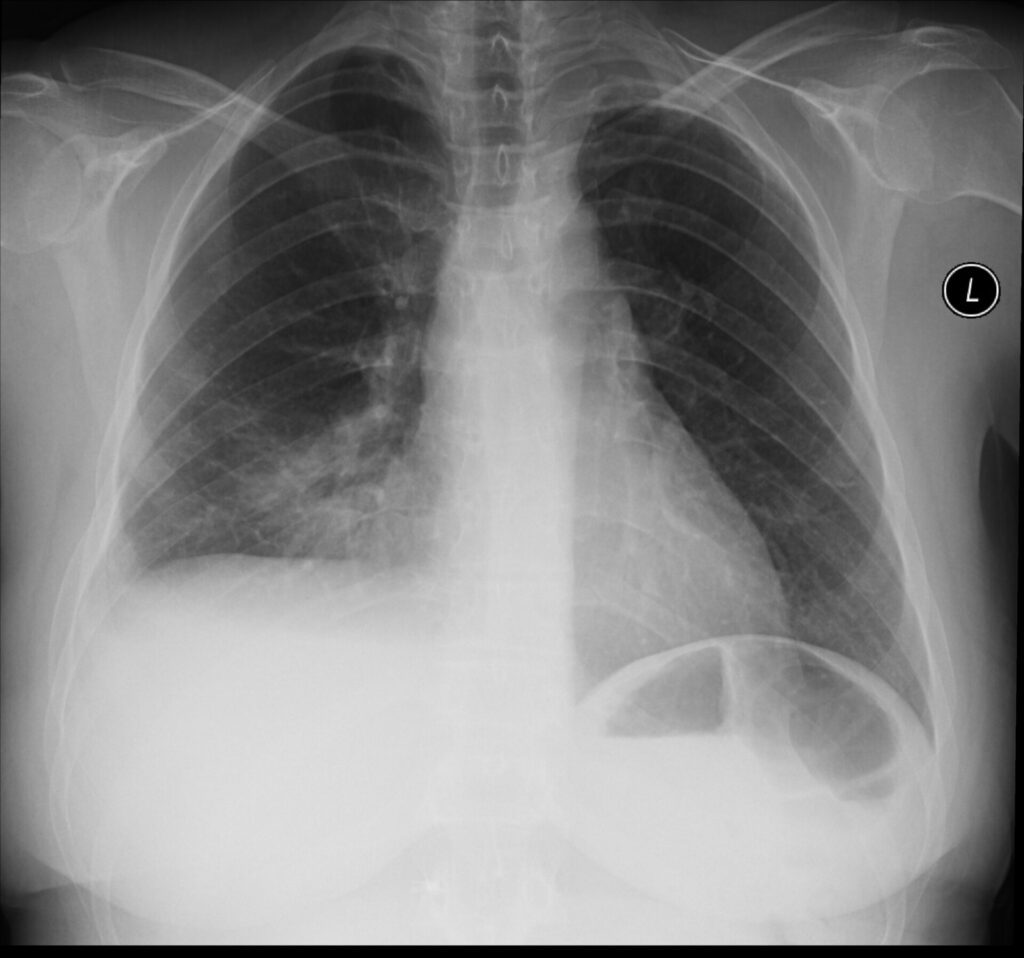

Die Bildgebung in der Medizin hat in den letzten Jahrzehnten rapide Fortschritte gemacht – von der klassischen Röntgenaufnahme über die […]